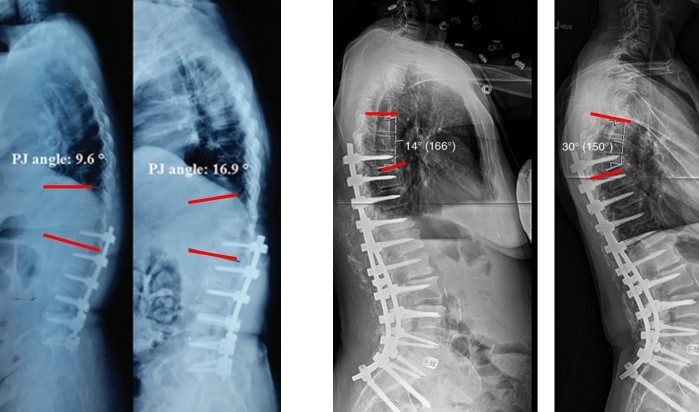

图7 术前-术后1个月-术后1个月外观

(4)固定棒选择

图8-11 相关文献表明,钴铬合金可提高固定强度及融合率,防止断棒,但也增加了PJK的发生率